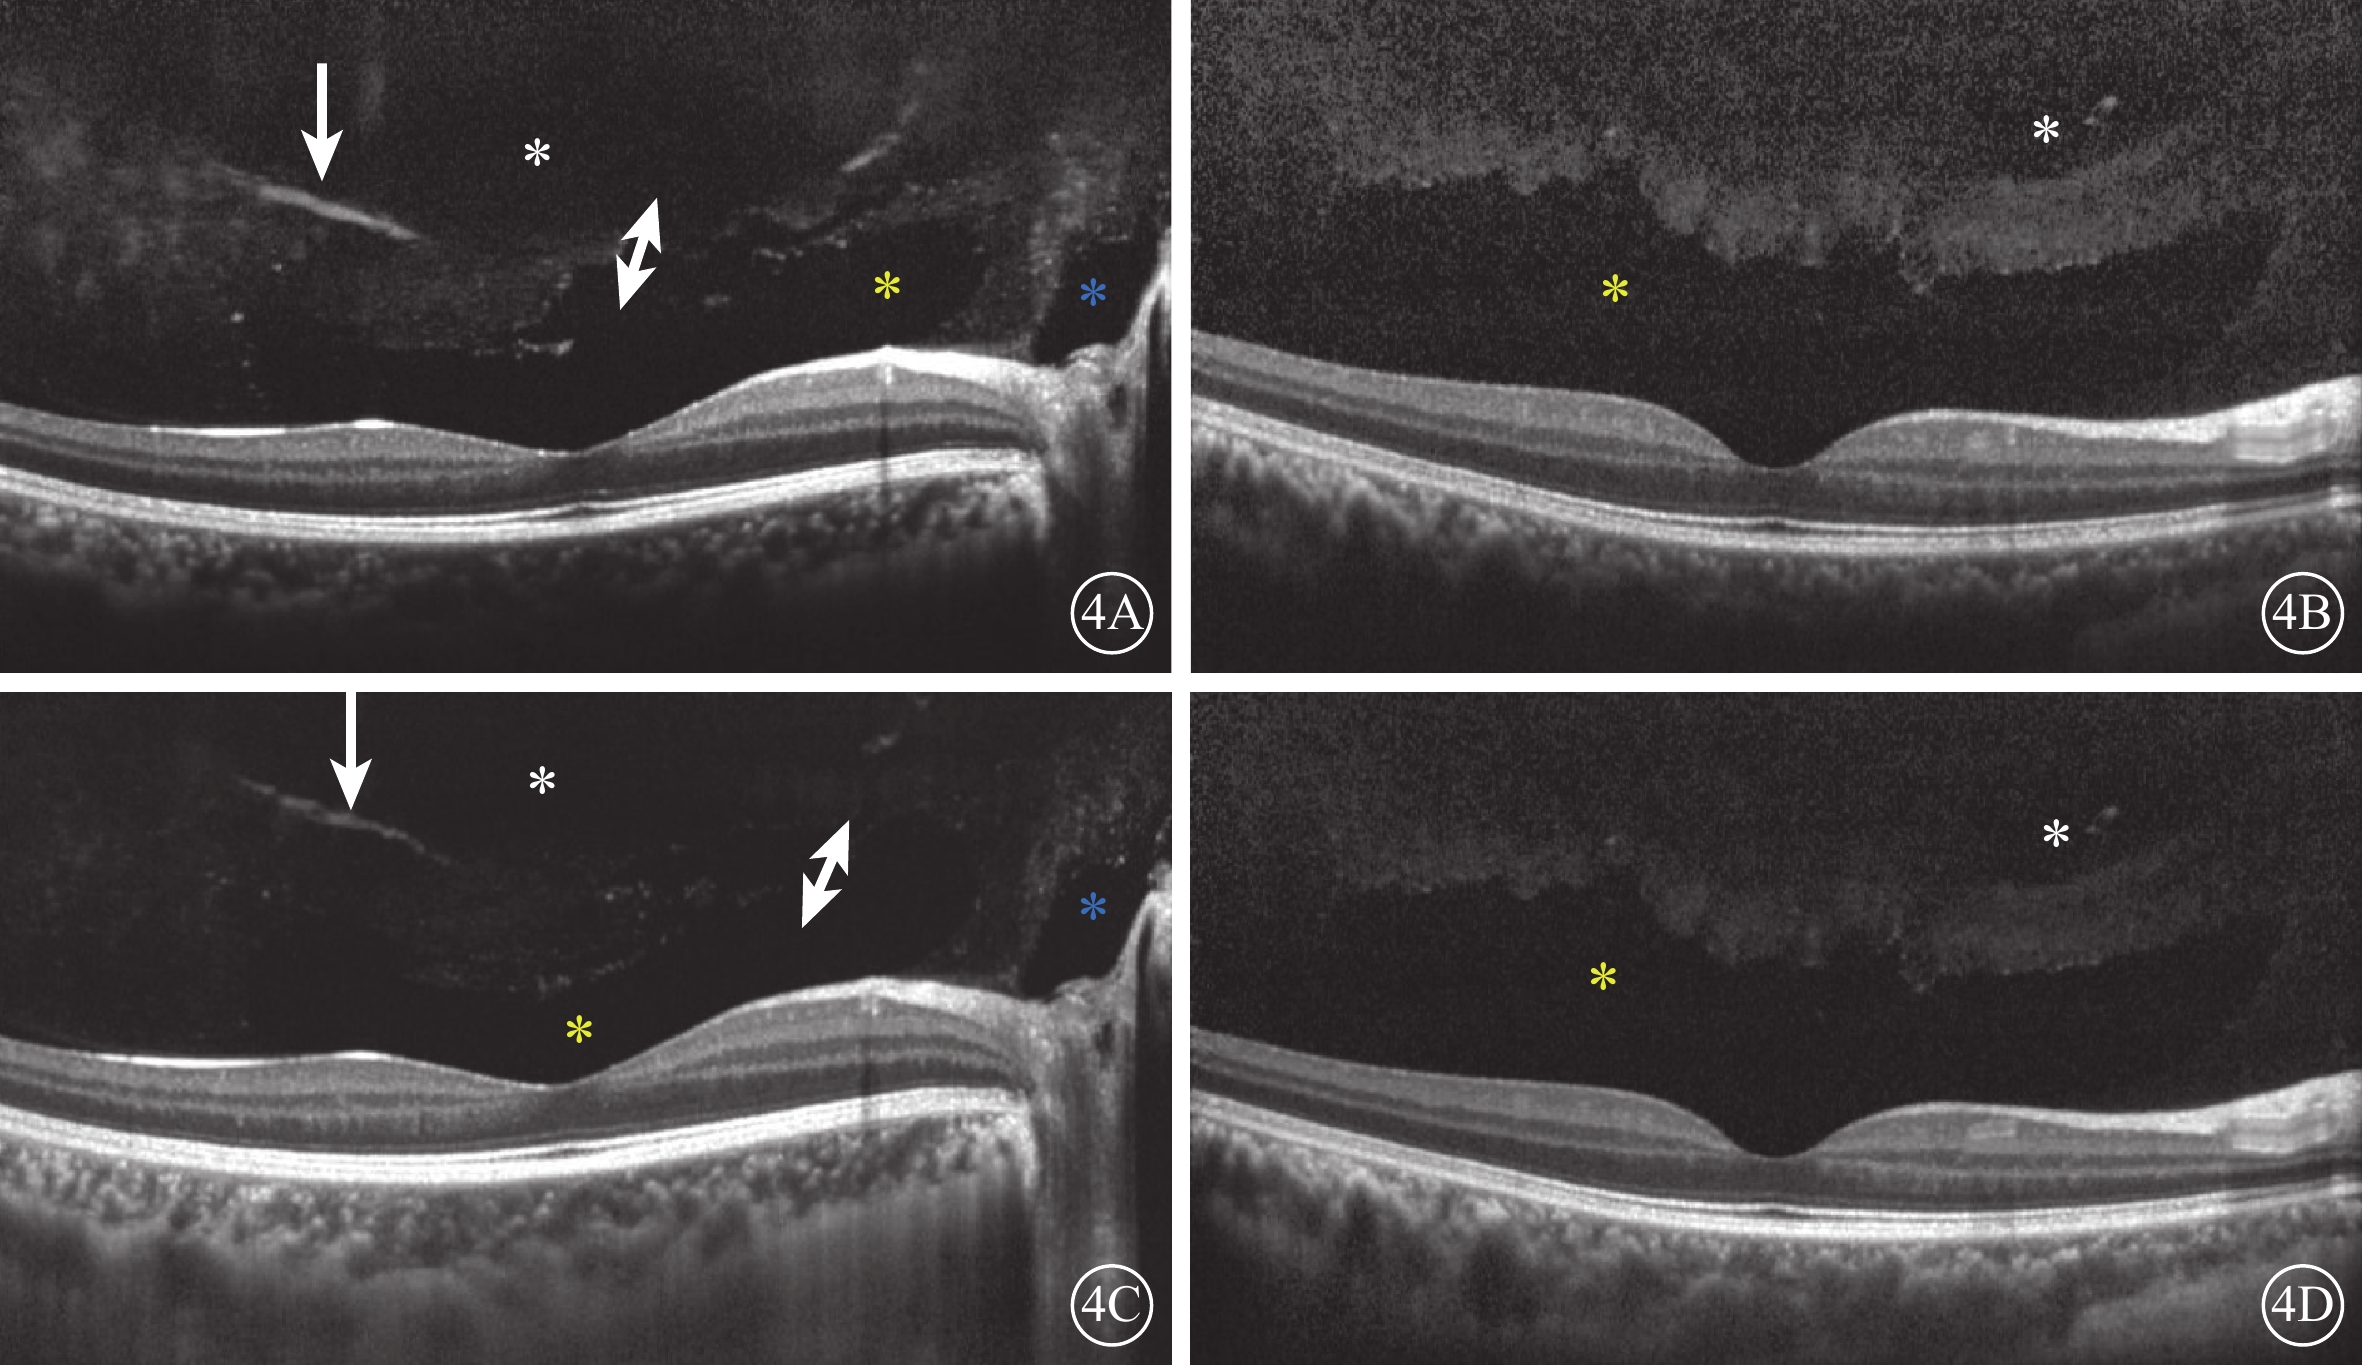

圖4

受檢眼SD-OCT像。4A、4B示后極部玻璃體掃描像;4C、4D示FDI掃描像。所有圖像均可見明顯PPVP(黃色星)和黃斑上囊(白色星)。4A、4C示部分Martegiani區(藍色星);部分玻璃體凝結(白箭),PPVP前界不光滑,與黃斑上囊出現連接通道(白色雙箭)。4C、4D示視網膜、脈絡膜成像較4A、4B清晰,但玻璃體成像清晰度較差

圖4

受檢眼SD-OCT像。4A、4B示后極部玻璃體掃描像;4C、4D示FDI掃描像。所有圖像均可見明顯PPVP(黃色星)和黃斑上囊(白色星)。4A、4C示部分Martegiani區(藍色星);部分玻璃體凝結(白箭),PPVP前界不光滑,與黃斑上囊出現連接通道(白色雙箭)。4C、4D示視網膜、脈絡膜成像較4A、4B清晰,但玻璃體成像清晰度較差

SD-OCT檢查,所有受檢眼常規檢查均未觀察到PPVP。后極部玻璃體掃描模式所采集的圖像可見PPVP結構清晰,表現為黃斑區前弱反射船形腔隙,前界為玻璃體膠原,后界為玻璃體皮質(圖2)。所有受檢眼PPVP鼻側存在一弱反射的無凝膠區域(Martegiani區),兩者之間有一隔膜將其分開。其中,單線掃描可見PPVP與Martegiani區之間存在連接通道(圖2)68只眼(66.0%);多線掃描可見所有受檢眼PPVP與Martegiani區存在連接通道,通道在某些層面出現(圖3)。PPVP前可見一個或多個黃斑上囊(圖2)16只眼(15.5%),其中黃斑上囊與PPVP之間相互連通(圖4)5只眼。PPVP伴玻璃體后脫離(PVD)(圖5)9只眼。采用FDI掃描模式進行檢查的21只眼,視網膜、脈絡膜成像清晰度較好,但玻璃體成像清晰度較差(圖4)。60只眼的PPVP平均最大水平距離為(6 895.7± 872.8)μm,平均垂直距離為(524.1±173.9)μm。

圖4

受檢眼SD-OCT像。4A、4B示后極部玻璃體掃描像;4C、4D示FDI掃描像。所有圖像均可見明顯PPVP(黃色星)和黃斑上囊(白色星)。4A、4C示部分Martegiani區(藍色星);部分玻璃體凝結(白箭),PPVP前界不光滑,與黃斑上囊出現連接通道(白色雙箭)。4C、4D示視網膜、脈絡膜成像較4A、4B清晰,但玻璃體成像清晰度較差

圖4

受檢眼SD-OCT像。4A、4B示后極部玻璃體掃描像;4C、4D示FDI掃描像。所有圖像均可見明顯PPVP(黃色星)和黃斑上囊(白色星)。4A、4C示部分Martegiani區(藍色星);部分玻璃體凝結(白箭),PPVP前界不光滑,與黃斑上囊出現連接通道(白色雙箭)。4C、4D示視網膜、脈絡膜成像較4A、4B清晰,但玻璃體成像清晰度較差